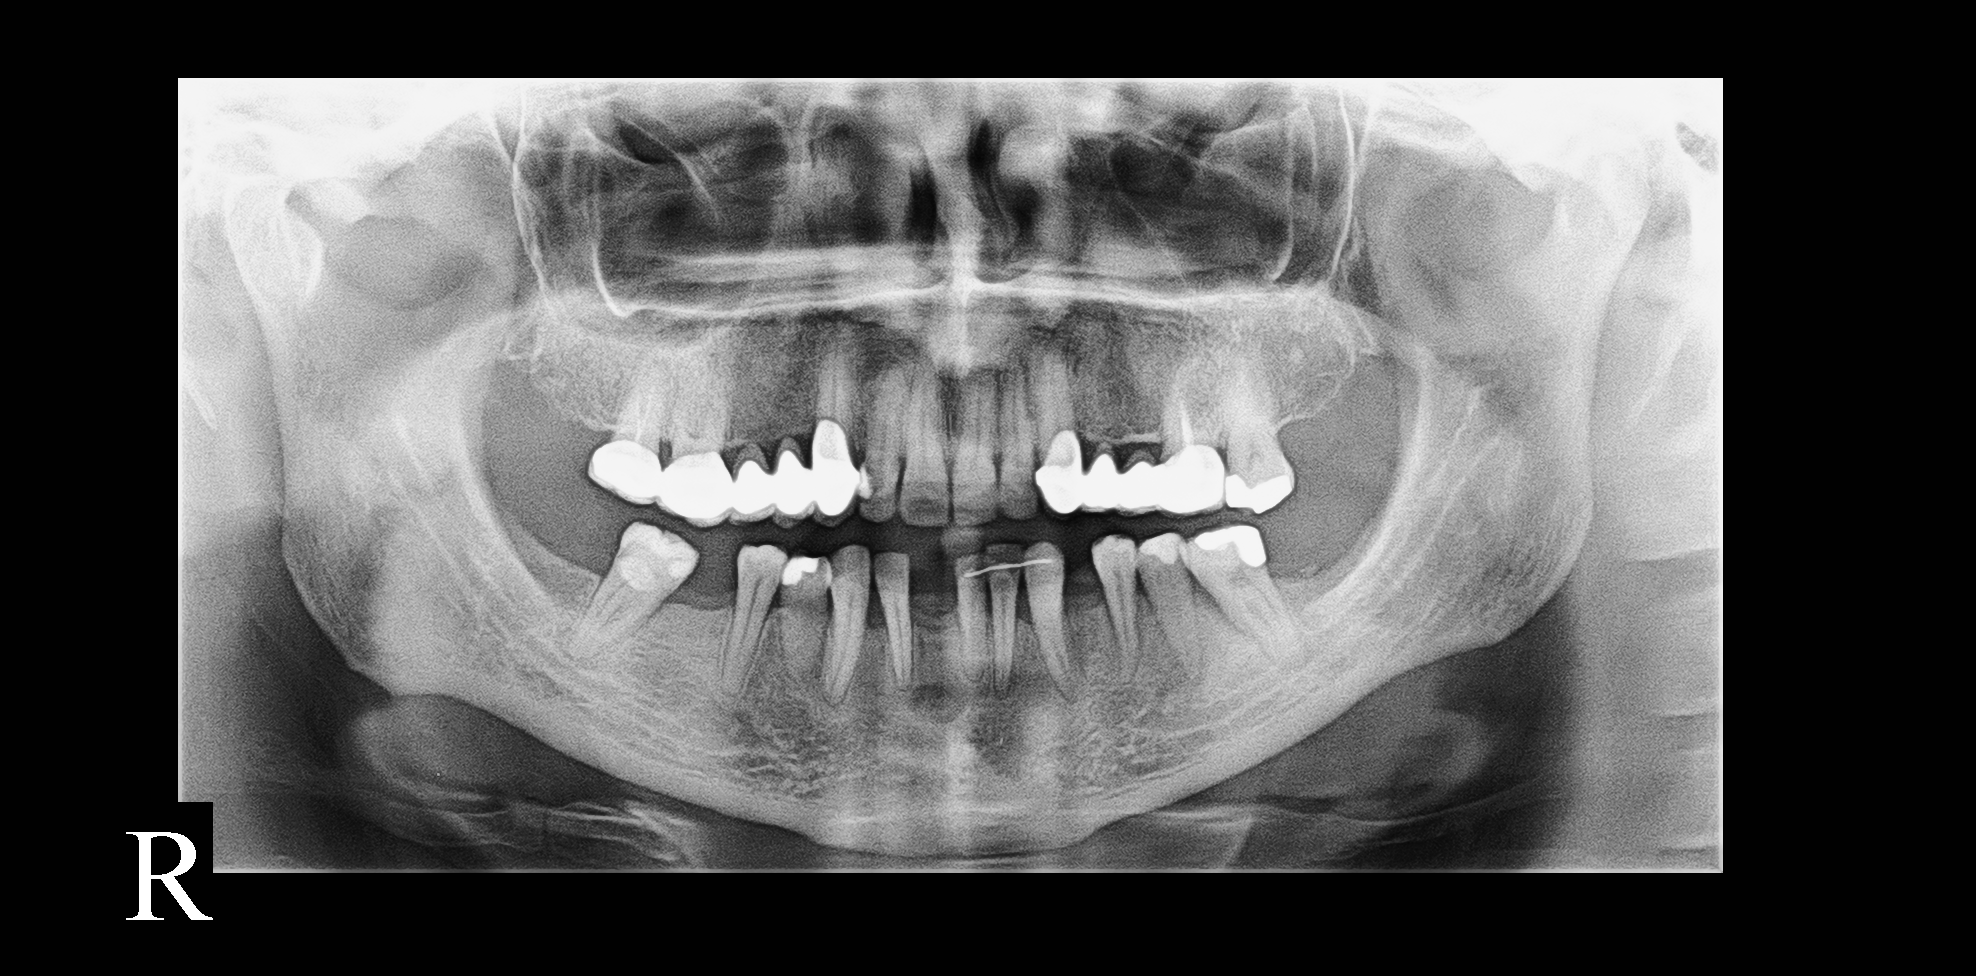

Ou escolha uma imagem de exemplo

Exemplo 1